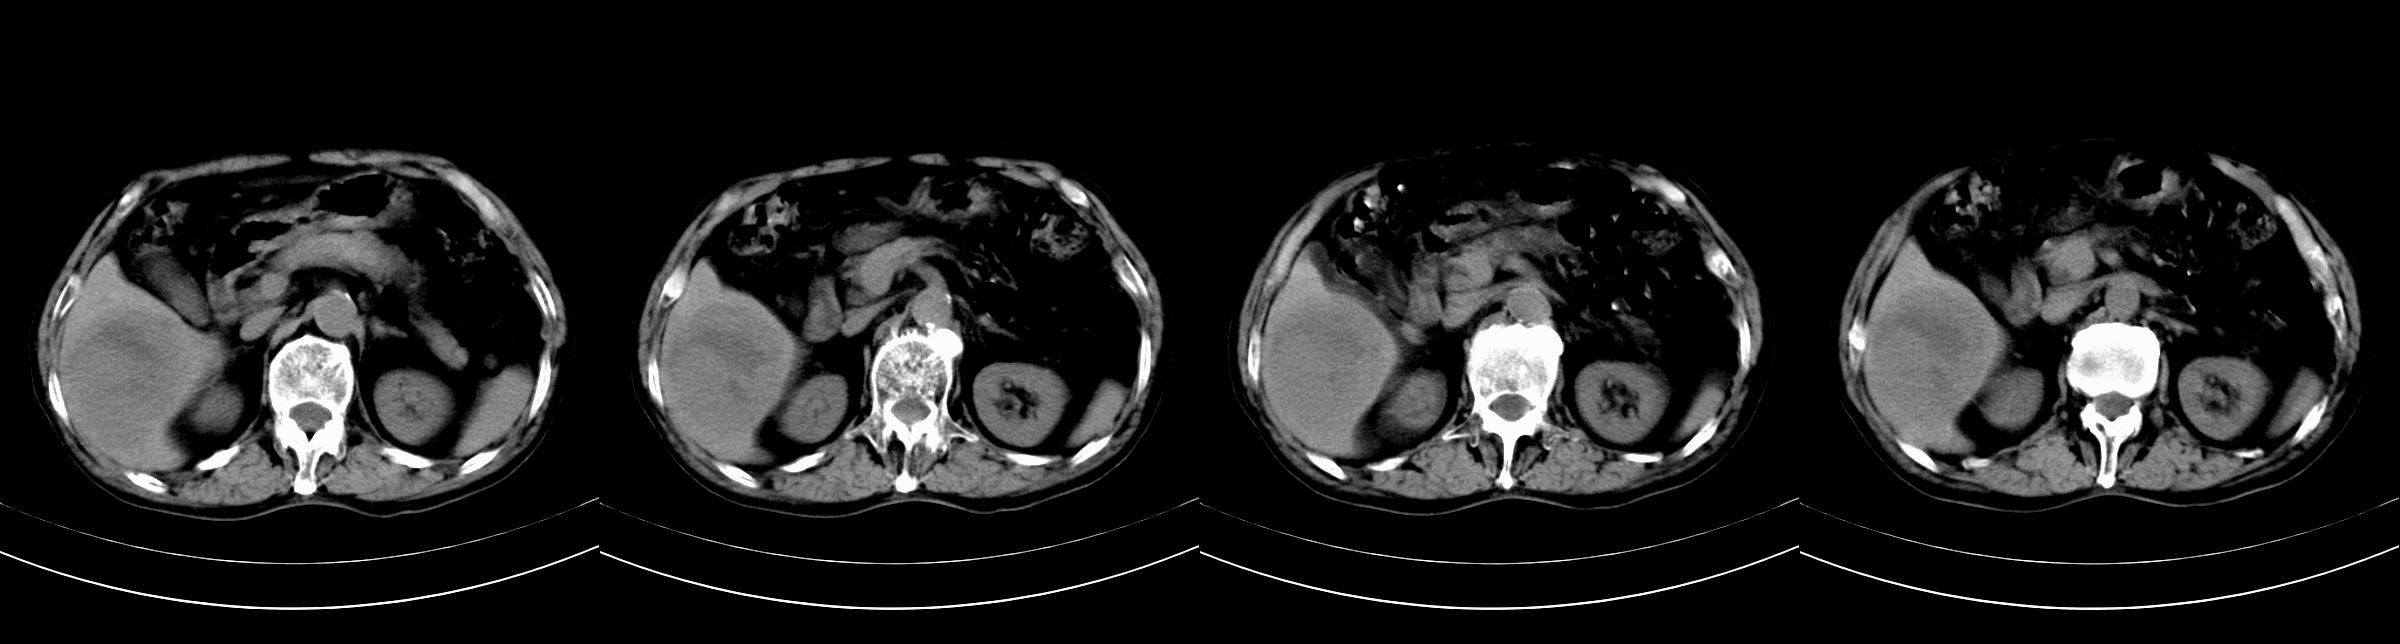

男,79y,无不适。体检发现肝脏占位。

肝内多发低密度结节,增强动脉期明显强化,门脉期逐渐下降,内有液化坏死区。

肝内多发低密度结节灶,增强动脉期明显不规则环状强化,;门脉期逐渐下降,肿瘤壁厚薄不一,内有坏死液化区。

诊断:肝转移癌可能

支持多发结节巨块型肝癌,建议查afp。

巨块型肝癌伴肝内转移.

诊断:典型的肝转移癌